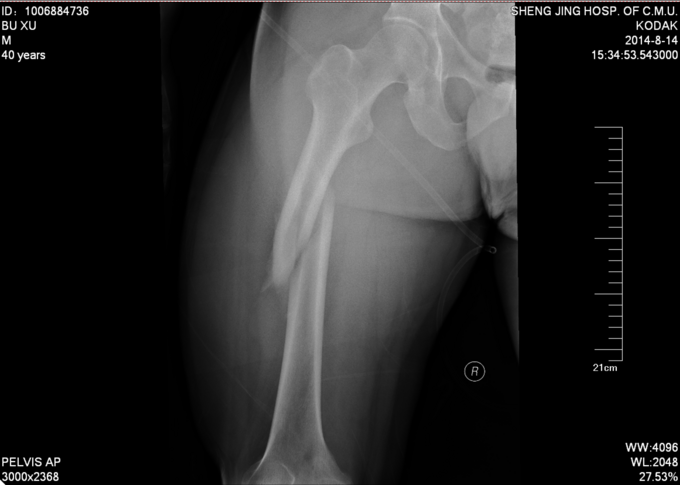

患者于2014-8-14 13:30左右,工作时不慎被重物砸伤,当时无法站立,自觉头晕,意识清楚,自觉大腿部疼痛,无法活动,被急送往我院急诊,经检查诊断为“右股骨干骨折”,给予对症处置,并请我科会诊,现患者为进一步诊治,转入我科病房,我科以“右股骨干骨折”为诊断收入院,患者伤后无昏迷,无恶心呕吐,无呼吸困难,至今未排便排气

右大腿肿胀,活动受限,压痛(+),骨擦音(+),骨擦感(+),可见异常活动,患肢皮肤感觉较健侧未见明显异常;足趾活动灵活,肌力正常,末梢循环可,足背动脉可触及。

诊断:右股骨干骨折 患者入院后急诊行右胫骨结节骨骼牵引术,术后维持患者长度,减轻患者疼痛,完善相关检查后,行右股骨干骨折闭合复位髓内针内固定术。